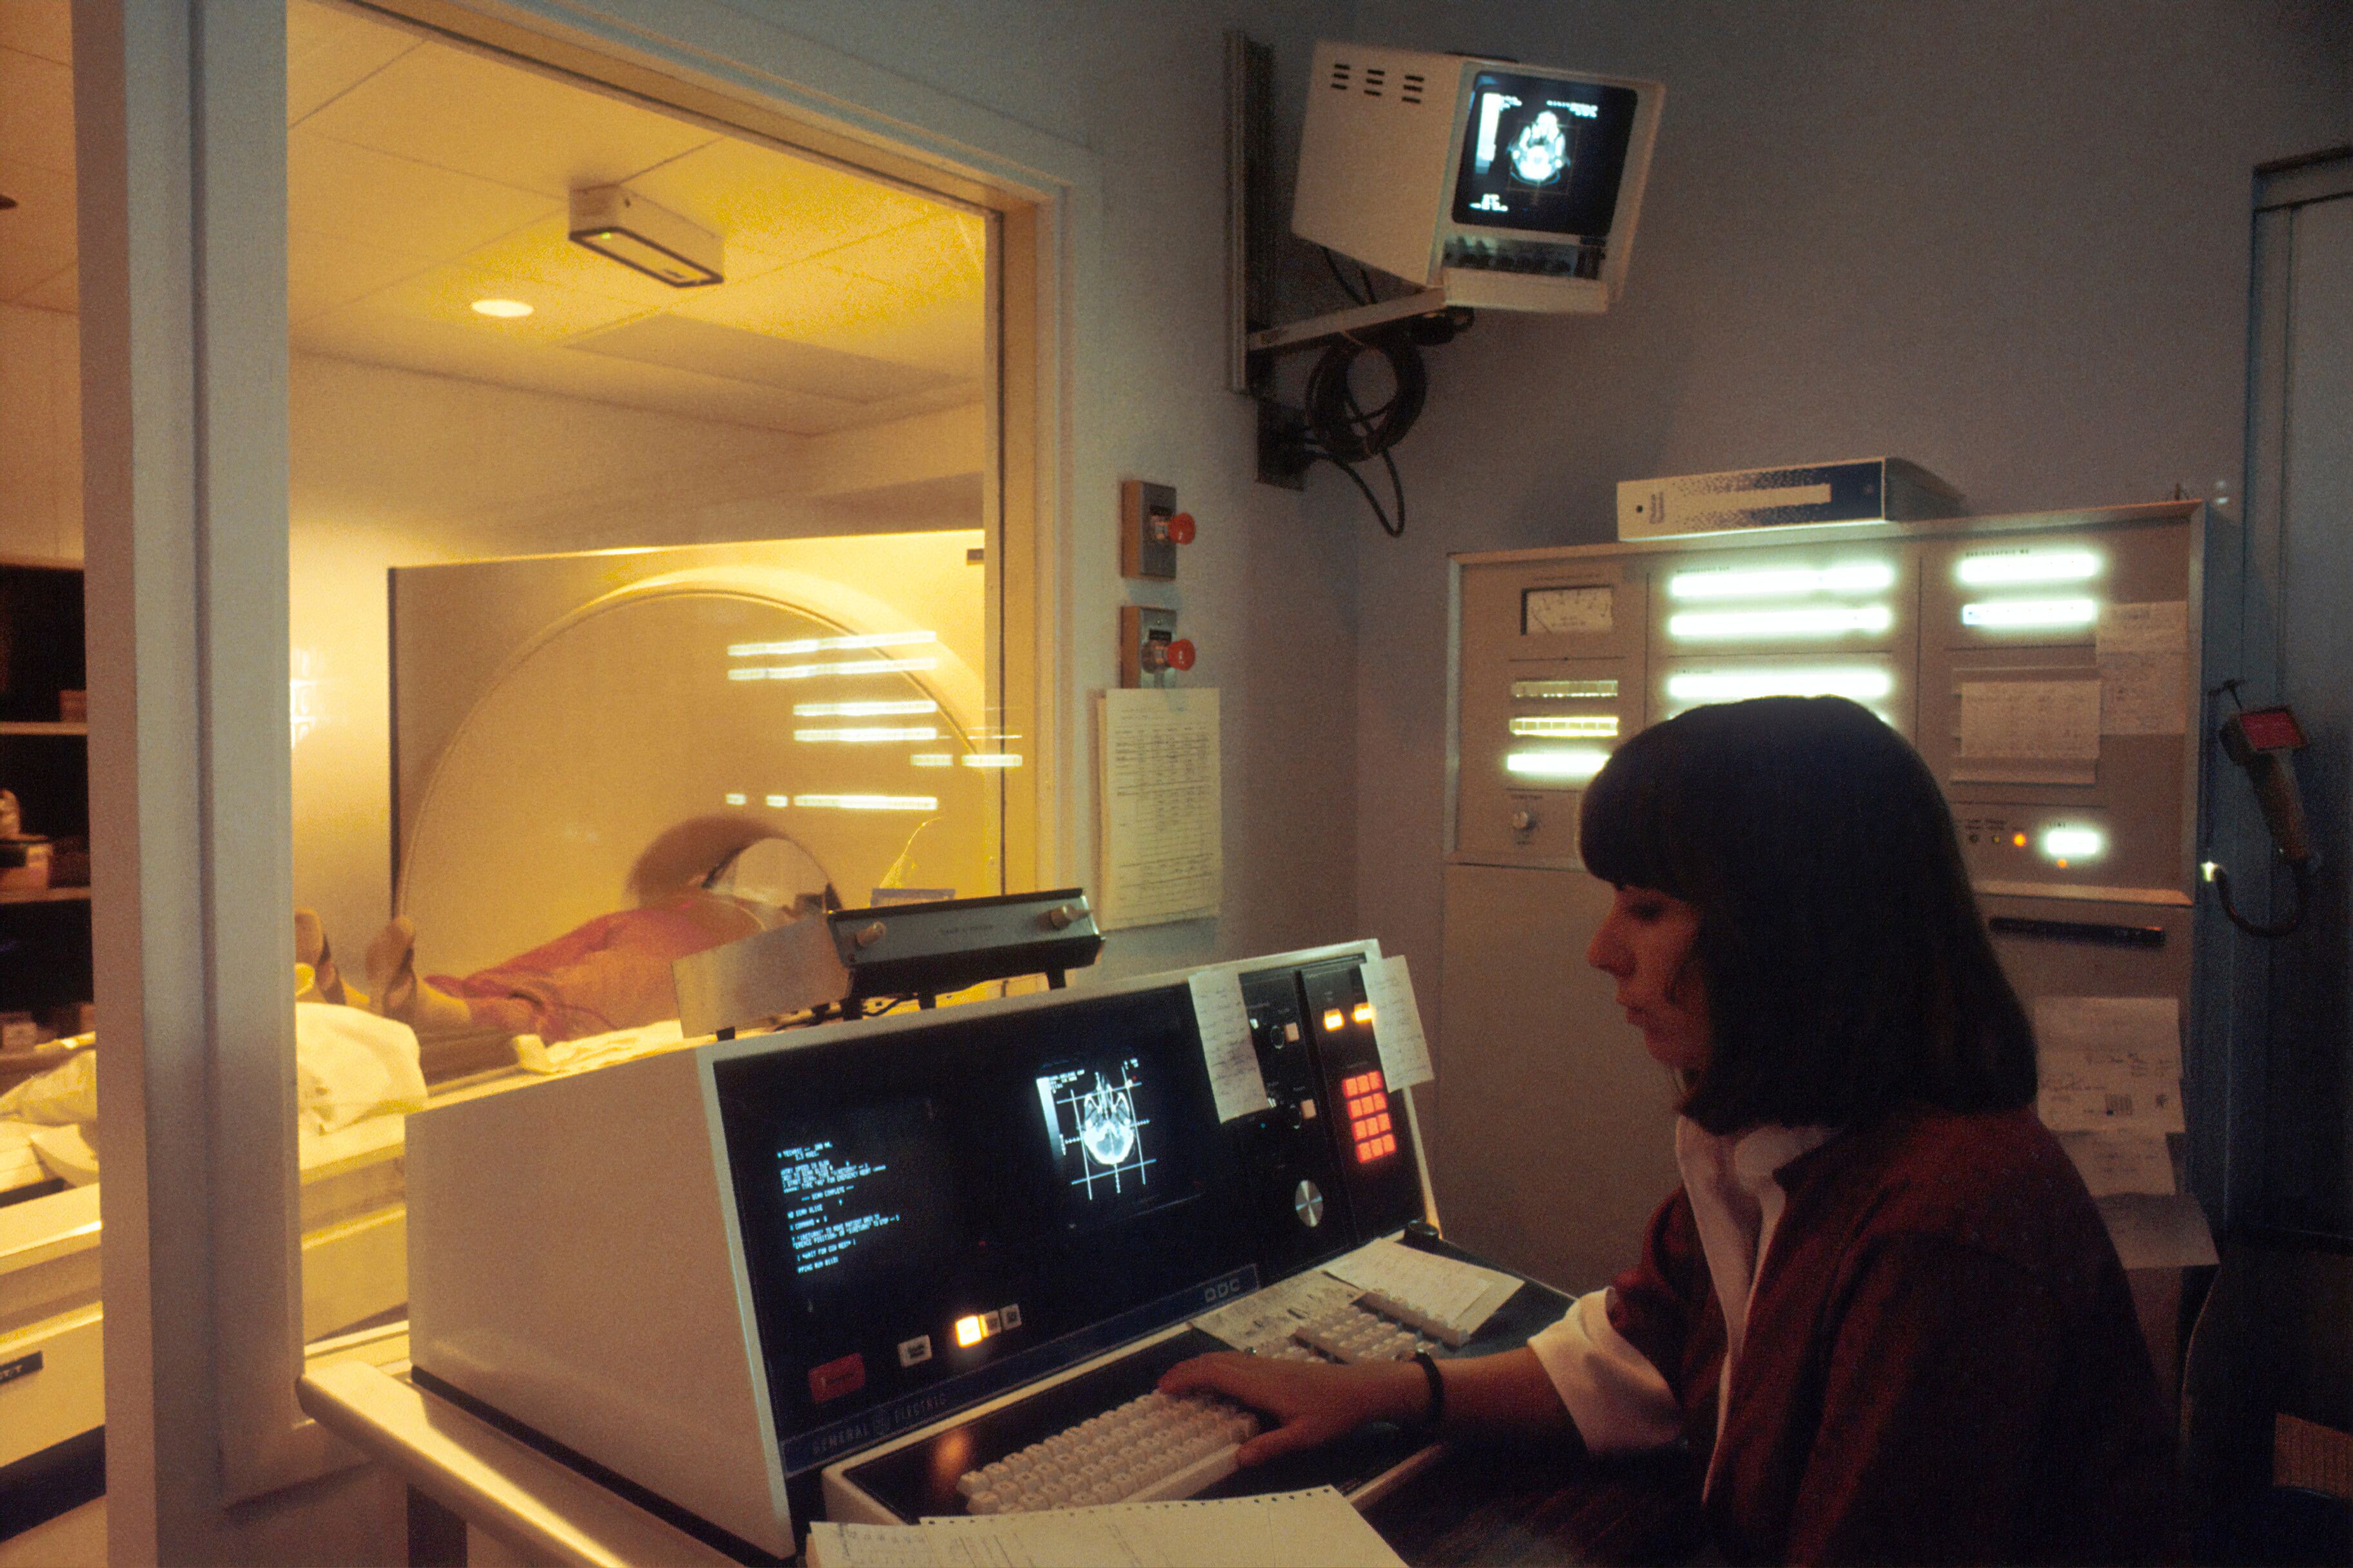

Ученые случайно открыли, что алмазная пыль светится при МРТ-исследовании. Это может стать безопасной альтернативой контрастному препарату на основе гадолиния. Сейчас при МРТ используют гадолиний, который накапливается в организме и может вызывать побочные эффекты. ferra.ru »